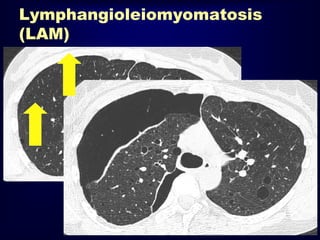

Lymphangioleiomyomatosis

HRCT Morphology

Thin-walled cysts (2mm - 5cm)

Uniform in size / rarely confluent

Homogeneous distribution

Chylous pleural effusion

Lymphadenopathy

in young women

(LAM).

A: PA chest radiograph shows a

right basilar pneumothorax and

two right pleural drainage

catheters. The lung volumes are

increased, which is

characteristic of LAM, and there

is diffuse reticular ILD.

B: CT scan shows bilateral thinwalled cysts and a loculated

right pneumothorax (P).

Lymphangioleiomyomatosis (LAM) HRCT Morphology Thin-walled cysts(2mm - 5cm) Uniform in size / rarely confluent Homogeneous distribution Chylous pleural effusion Lymphadenopathy in young women